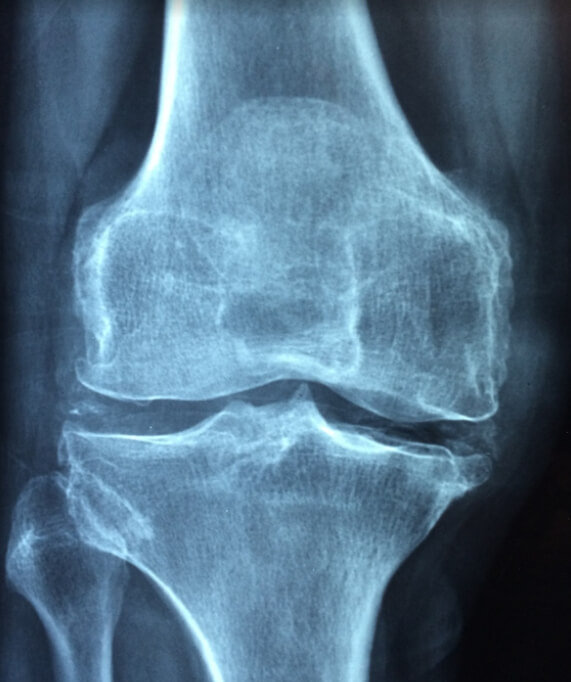

무릎과 어깨 관절이 여기에 속합니다. 관절 문제나 불편함은 여러 가지 원인을 가질 수 있습니다. 나이와 관련된 마모로는 시간이 지나면 관절을 완충하는 연골이 마모되어 골관절염과 같은 질환으로 이어질 수 있습니다.

부상으로는 골절이나 탈구와 같은 외상이나 부상이 관절 내 구조물을 손상시키며 통증과 움직임 제한을 초래할 수 있습니다.